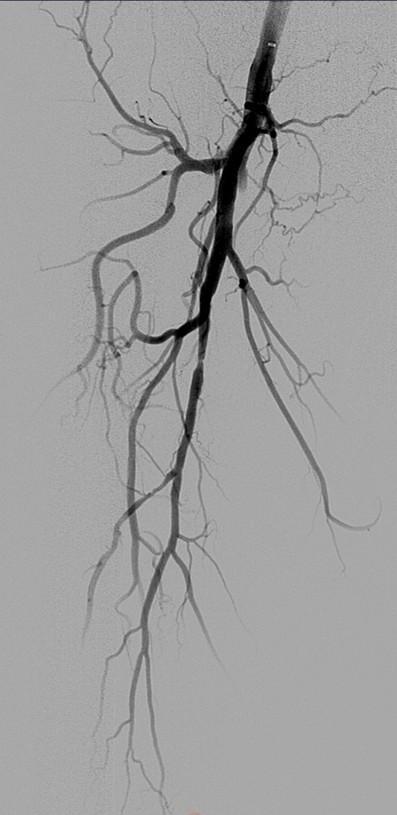

基于此,我们提出了“DEC”(Drug-Eluting Covered Stent)策略,即联合使用药物洗脱支架(DES, 如 Eluvia™)。该策略旨在:

利用 VB 的物理隔绝优势克服夹层与 recoil;

利用 DES 的药物缓释优势抑制两端及重叠区的内膜增生;

同时,DES 的裸支架平台对近端股深动脉等侧支影响更小。

支架植入:遵循“由远及近”原则,先放置远端 DES,再覆盖中段 VB,最后处理近端。利用 Eluvia 的可调节性优化重叠。